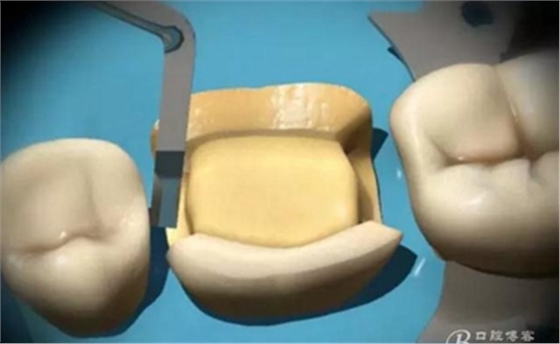

制作完成

高嵌體

試戴

檢查鄰接

高嵌體病例圖片